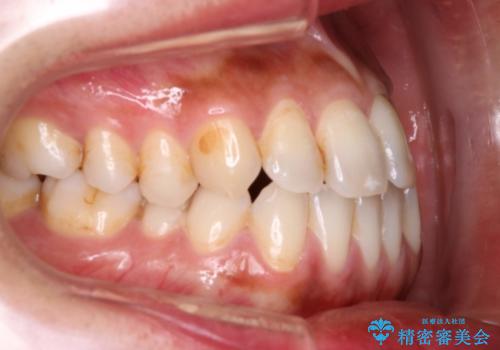

Invisalign インビザライン によるガタつき、受け口傾向の改善

- 拡大・IPRによるスペースゲインを主とした非抜歯・マウスピース矯正を計画しました。

奥歯の位置関係の修正は難儀することが多いマウスピース矯正ですが、割とスムーズに奥歯の位置関係の修正をすることができました。

クロスバイトもきれいになり、きれいな歯並びとなりました。